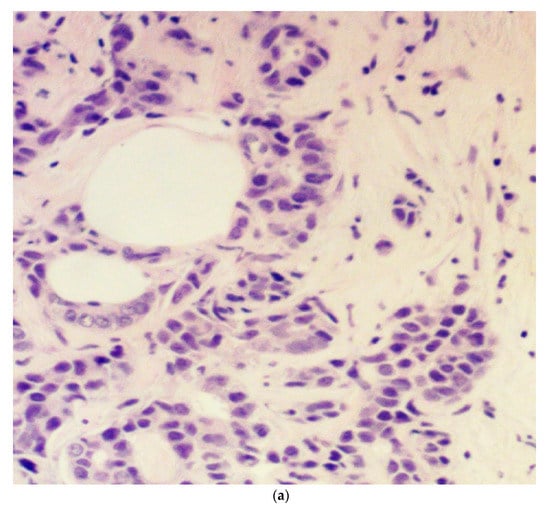

Tumor budding was examined in eosin and hematoxylin sections of the initial diagnostic biopsy specimens of patients. These specimens were obtained by an interventional radiologist through a core needle biopsy under ultrasound guidance before the initiation of treatment. The presence or absence of budding and the grade (intermediate/high-grade tumor budding: 5 or more buds per 20× power field in a hotspot area of 0.785 mm2; low-grade tumor budding: less than 5 buds per 20× power field in a hotspot area of 0.785 mm2) were reviewed with the same microscope by two experienced general pathologists and recorded in the study database. We elected to use a 5-bud limit for the categorization of tumor budding grade based on the recommendations of the International Tumor Budding Consensus Conference for colorectal cancer [17]. In case of a discrepancy between the two pathologists, the overall result was decided by consensus. The agreement between pathologists was excellent (kappa statistic 0.89) for the presence or absence of budding and very good (kappa statistic 0.70) for the degree (grade) of budding. A bud was defined as 1 isolated tumor cell or up to 5 cells in clusters detached from the main tumor mass (Figure 1).

Figure 1.

Microphotograph examples of a patient with low-grade budding (a) and a patient with high-grade budding (b). Arrows pinpoint representative buds.